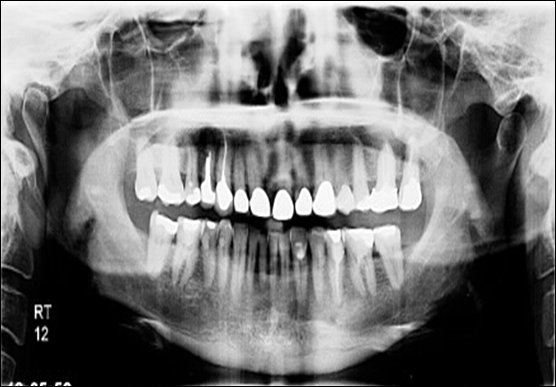

Multiple Root Problems